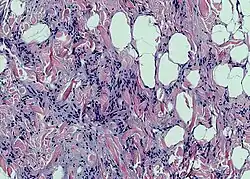

| Photomicrograph of a spindle cell lipoma. | |

According to histology, the lesion is made up of tiny, homogeneous spindle cells and mature adipocytes combined with eosinophilic collagen bundles inside a myxoidstroma. According to immunohistochemical staining, the spindle cells are positive for CD34 but negative for S-100 protein.[3]